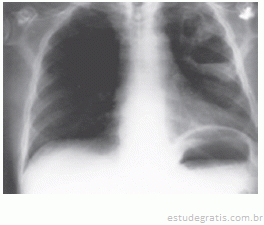

Um paciente de 48 anos foi admitido na UTI com história de uma forte gripe até uma semana atrás. Apresentava síndrome febril, tosse, dispnéia; há uma hora, apresentou hipotensão arterial. Baseado na história e na imagem, podemos afirmar o diagnóstico de: